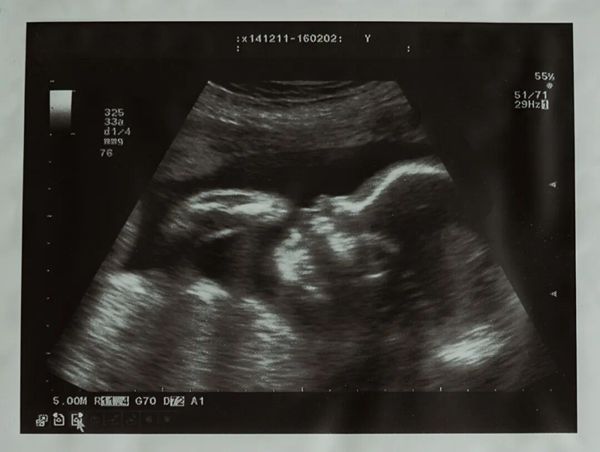

根据陈女士目前临床症状、检验结果及既往复发性流产病史,建议患者予低分子肝素抗凝治疗。 陈女士也很配合说一切听医生的建议,治疗期间复查彩超情况提示胚胎发育速度有改善,目前基本与停经时间相符,在监测胚胎发育的同时也给陈女士定期复查易栓症及肝功能。

孕12周时NT结果正常,抗磷脂抗体仍为阳性,其他易栓症指标未见明显异常。考虑患者目前胚胎发育均符合孕周,抗磷脂抗体滴度不高,建议患者停低分子肝素换为口服阿司匹林治疗至孕36周停药。

患者目前已处孕晚期,诉产检一切正常,就等待着宝宝的到来了。